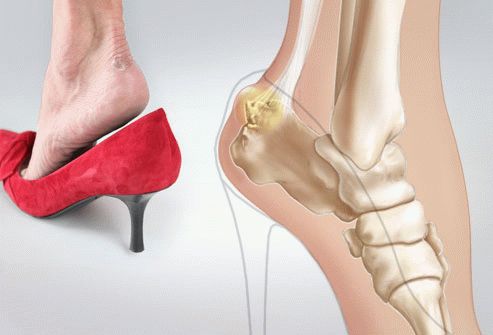

Шишка над пяткой давит на слизистую сумку между пяточным сухожилием и пяточной костью, что вызывает болезненные ощущения и отечность. Не все воспалительные процессы приводят к образованию наростов; иногда это связано с другими проблемами, симптомы которых можно устранить другими способами. При обычном воспалении слизистой также могут возникать неприятные ощущения.

- Ношение тесной обуви может способствовать образованию наростов. Она вызывает дискомфорт и может привести к образованию мозолей и более серьезным последствиям. Высокий и жесткий задник обуви часто становится причиной шишек, поэтому выбор обуви следует делать с осторожностью, иначе исправить последствия будет сложно.